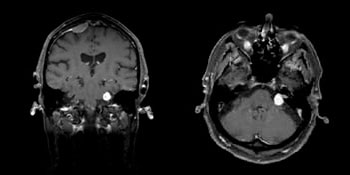

På billederne her ses acusticusneurinomet som en lys plet.

Den endelige diagnose stilles ved hjælp af en MR-skanning. MR-skanninger udføres på røntgenafdelinger på de fleste større sygehuse. Ved en sådan skanning kan man finde knuder, der kun er få mm store, og som måske endnu ikke er vokset ud af den indre øregang. Man skal regne med, at der kan være en måleusikkerhed på op til 2 mm.